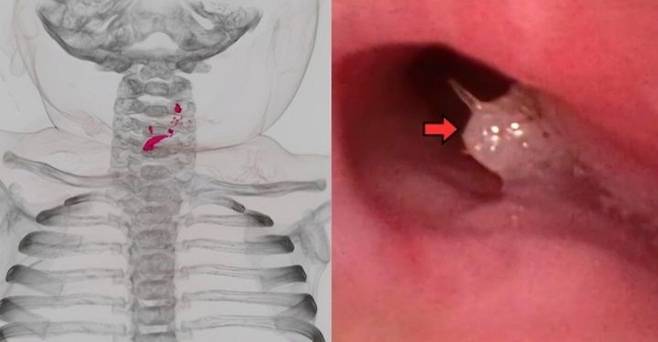

정밀 검사 결과 기관지에는 물고기로 추정되는 백색 이물질이, 식도에는 가시 2개가 박혀 있었다. 또한 물고기 가시와 비늘로 보이는 여러 이물질이 식도 점막을 손상시켜 찢어지고 구멍이 난 상태였다.

의료진은 기관내 삽관과 집게, 식도위십이지장내시경 등을 이용해 가시와 비늘을 제거했다. 시술 후 아기는 중환자실에서 치료를 받았으며, 입원 19일째 일반 병실로 옮겨졌다. 25일째에는 일반식을 섭취할 수 있을 만큼 회복해 퇴원했으며, 이후 추적 검사에서도 별다른 합병증은 발견되지 않았다.